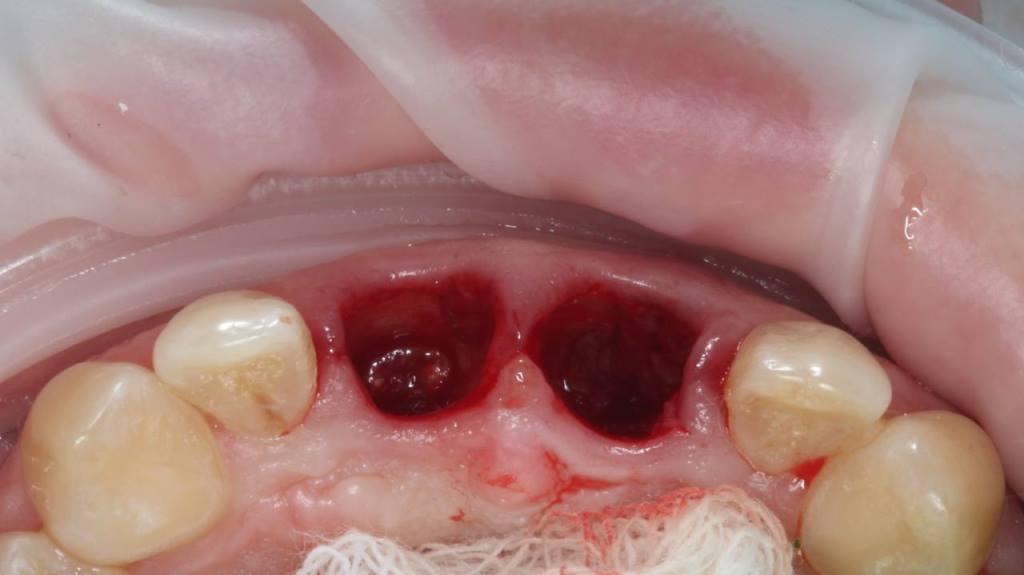

И существует такая методика как IDR - immediately dentoalveolar reconstruction. Суть методики заключается в том, что при дефиците костной ткани мы заполняем пространство костной и мягкой тканями, взятыми с бугра верхней челюсти пациента (за последним зубом). Берется трехслойный трансплантат, и здесь важно до операции по компьютерной томограмме оценить объем донорской зоны. При этом не делается никаких разрезов во фронте. Зубы удаляются очень атравматично, аккуратно, чтобы сохранить все имеющиеся ткани.

Фото 3, 4, 5.

Но! Воссоздать, восстановить то, что дано природой всегда сложнее, чем сохранить! А сохранить есть что: объем костной ткани, уровень мягких тканей - симметрию зенитов и межзубные сосочки! Во фронтальном отделе это критически, экстремально важно. Особенно при высокой линии улыбки, когда обнажаются не только зубы, но и десна.